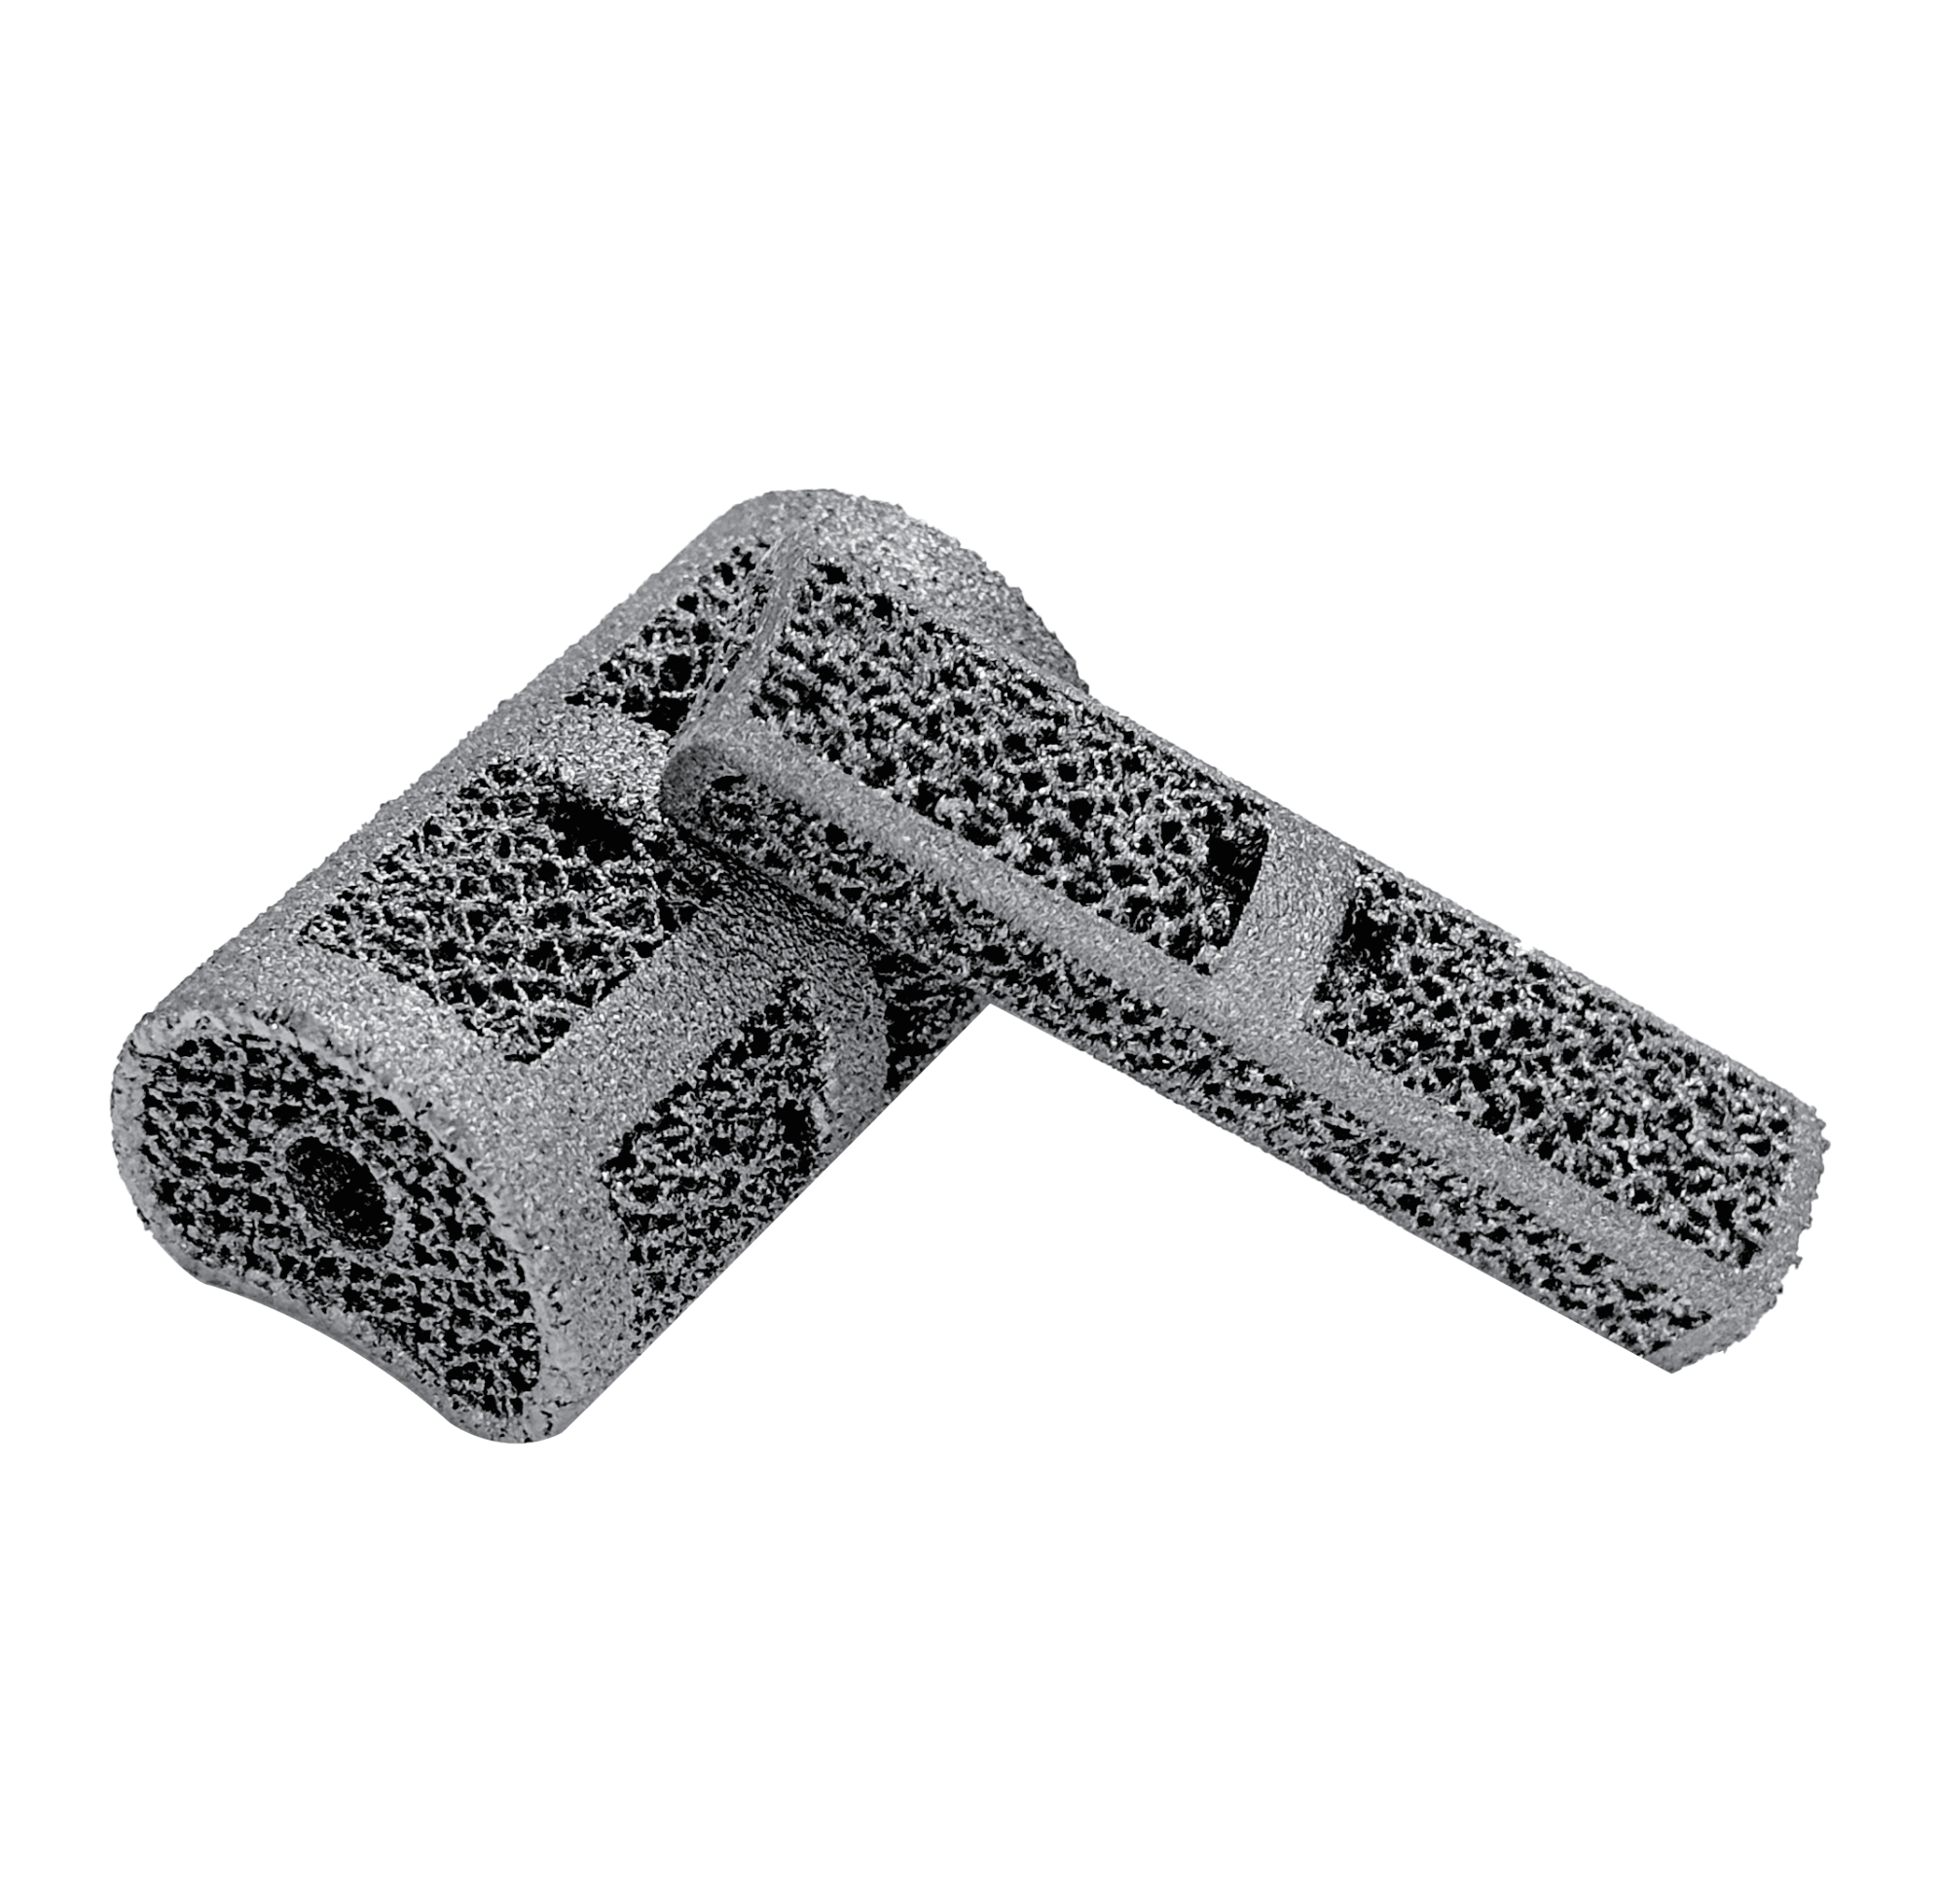

Porous Vertebral Body Prosthesis